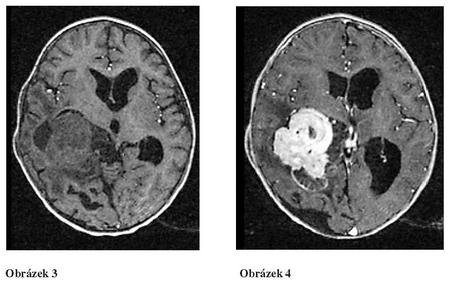

Hlavním projevem jsou příznaky obstrukčního hydrocefalu, který je přítomen při diagnóze u 75-90% případů. CT obraz CPP je poměrně specifický, tumor je dobře ohraničený od okolní mozkové tkáně, obsahuje kalcifikace a homogenně vychytává kontrast (na rozdíl od ependymomu). Při MRI vyšetření jsou papilomy isodensní s mozkovu tkání (Tl-vážený obraz), po gadoliniu nádor intenzivně světle enhancuje (obrázek 3 a 4). Hranice mezi nádorem a mozkovou tkání je v případě CPC nezřetelná, nejedná se ovšem o univerzální nález.